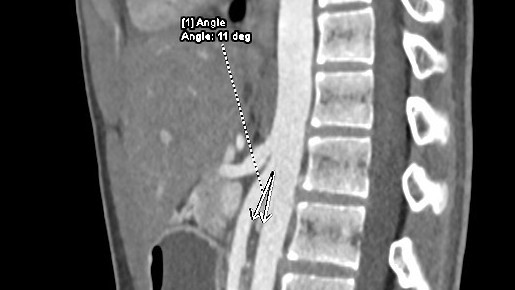

Sau chụp CT, bệnh nhân được chẩn đoán mắc một hội chứng hiếm gặp có tên là hội chứng động mạch mạc treo tràng trên, hay còn gọi là hội chứng Wilkie. Đây là trường hợp hiếm gặp của tình trạng tắc nghẽn đường tiêu hóa trên, do sự gập góc giữa động mạch mạc treo tràng trên và động mạch chủ bụng gây chèn ép đoạn D3 tá tràng. Nếu chậm trễ trong chẩn đoán và điều trị có thể dẫn đến biến chứng rối loạn điện giải và kiềm toan, suy kiệt…

Kết quả CT cho thấy góc động mạch mạc treo tràng trên – động mạch chủ của người bệnh chỉ 110 so với bình thường là 300.

Ở người lớn, triệu chứng của hội chứng Wilkie xảy ra khi góc động mạch mạc treo tràng trên – động mạch chủ bụng giảm dưới 200. Ở bệnh nhân trẻ em, góc này còn nhỏ hơn.